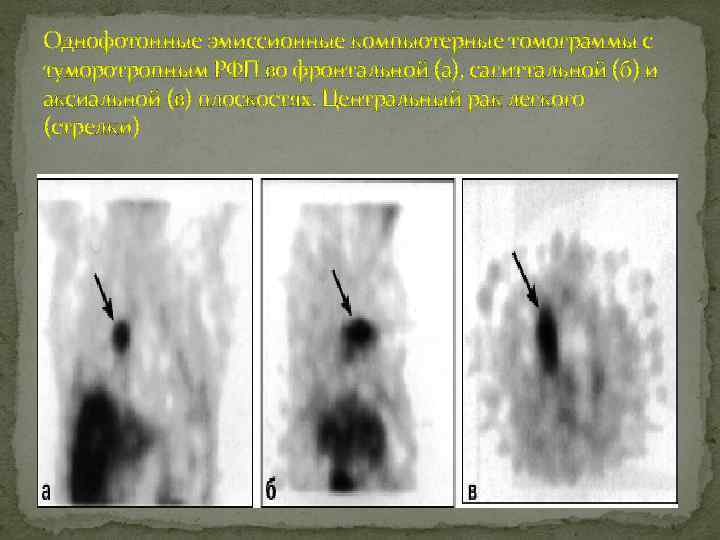

Рак легкого центральный Сцинтиграфия с туморотропными РФП и ПЭТ: избирательная аккумуляция РПФ в первичной опухоли и в метастатически пораженных лимфатических узлах

Однофотонные эмиссионные компьютерные томограммы с туморотропным РФП во фронтальной (а), сагиттальной (б) и аксиальной (в) плоскостях. Центральный рак легкого (стрелки)